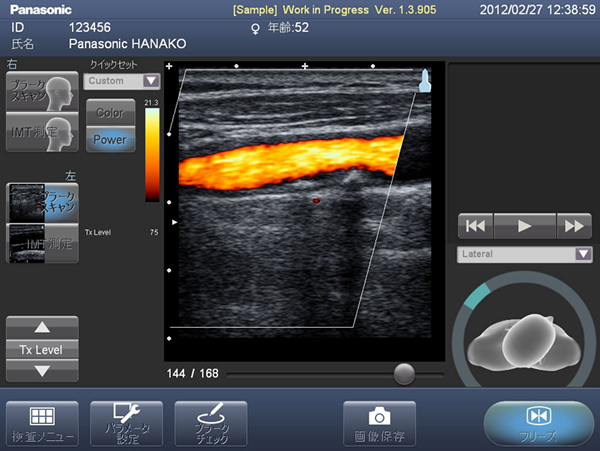

画面イメージ(カラードプラと日本語表示)

2. カラードプラ機能の搭載によりプラークをわかりやすく描写

血流をカラーで表示することで、プラークの目視診断の精度が向上します。

※7:カラードプラ機能:カラードプラ法(CDI color doppler imaging)は、生体内血行動態に色を付けBモード画像上に重ね合わせながらリアルタイムで表示する方法。